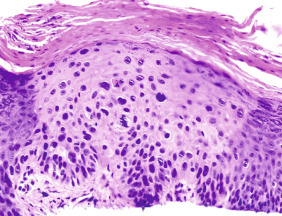

Squamous cell carcinoma in situ (SCCIS), also known as Bowen disease, is intraepidermal form of squamous cell carcinoma. SCCIS can occur on the skin ( Fig. 29.1 ) and mucous membranes. Multiple causative factors are associated with SCCIS, including ultraviolet light, arsenic ingestion, and infection with oncogenic strains of HPV. SCCIS is more common in immunocompromised persons.

The primary lesion consists of a sharply defined scaly papule or plaque, with variable erosion or ulceration ( Figs. 29.2–29.4 ). There may be inflammation and erythema due to the host response.